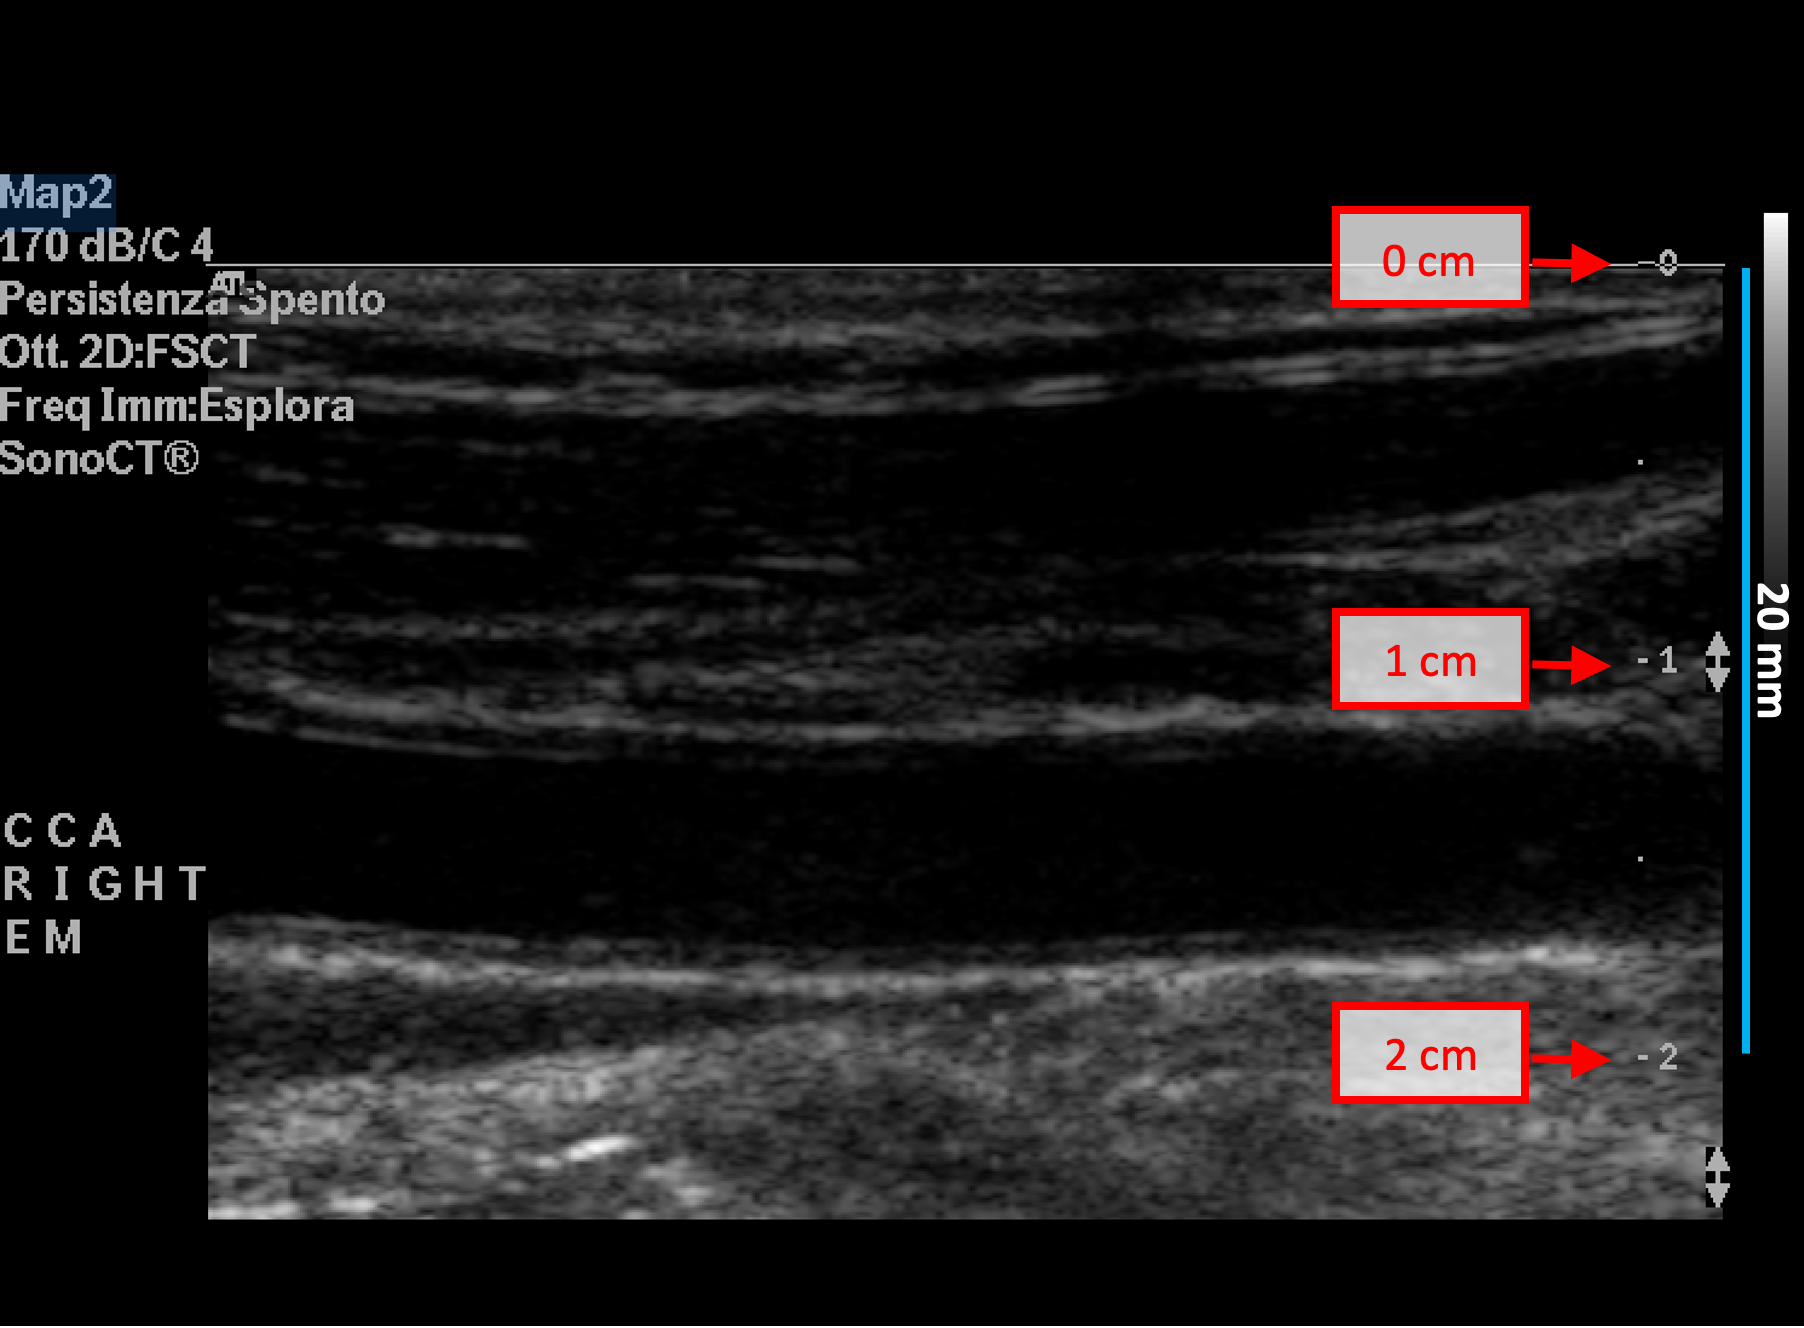

B-mode calibration examples

The following images show examples of calibrations of the b-mode image. Graphic items in red shows where you can find the information about the depth of the image in the ultrasound image.